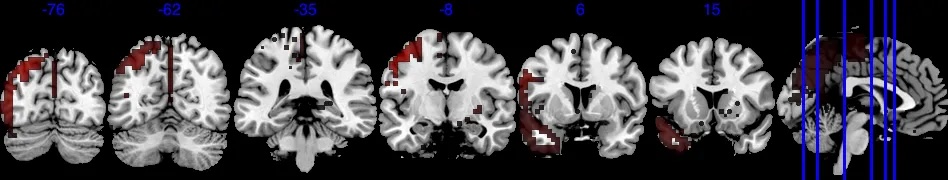

For a visual representation, Figure 3(a) shows the voxel level PIP in the sagittal plane. The highlighted red regions represent voxels with greater than 0.95 PIP. Figure 3(b) presents the effect size of , with the highlighted area in the range . Note that from Figure 3(b), voxels with PIP greater than 0.95 also correspond to voxels with a larger absolute value of effect size. We notice that the activation region (defined by voxel level PIP greater than 0.95) has a negative effect . This can also be validated by the scatter plot in Section D in the Supplementary Material, where the image intensity generally has a negative association with age across all individuals.

Based on our results, we have the following general interpretations: (i) when controlling for the confounders, age has a negative impact on the neural activity for emotion-related tasks; (ii) the negative effect reflected from each voxel is of very small scale, shown as in Figure 3(b), indicating a very low voxel level signal-to-noise ratio; (iii) the top 5 brain regions with the highest RLAR are (a) right intracalcarine cortex, right supracalcarine cortex, and left Temporal fusiform cortex, anterior division, all considered as critical areas for high-level visual processing including face recognition; (b) left temporal fusiform cortex, anterior division, a key structure for face perception, object recognition, and language processing (Weiner and Zilles, 2016); and (c) right inferior temporal gyrus, anterior division, an area for language and semantic memory processing, visual perception, and multimodal sensory integration (Onitsuka et al., 2004). These top 5 regions are also consistently identified in the sensitivity analysis when using half of the data as training data, see Section 4.4.1.